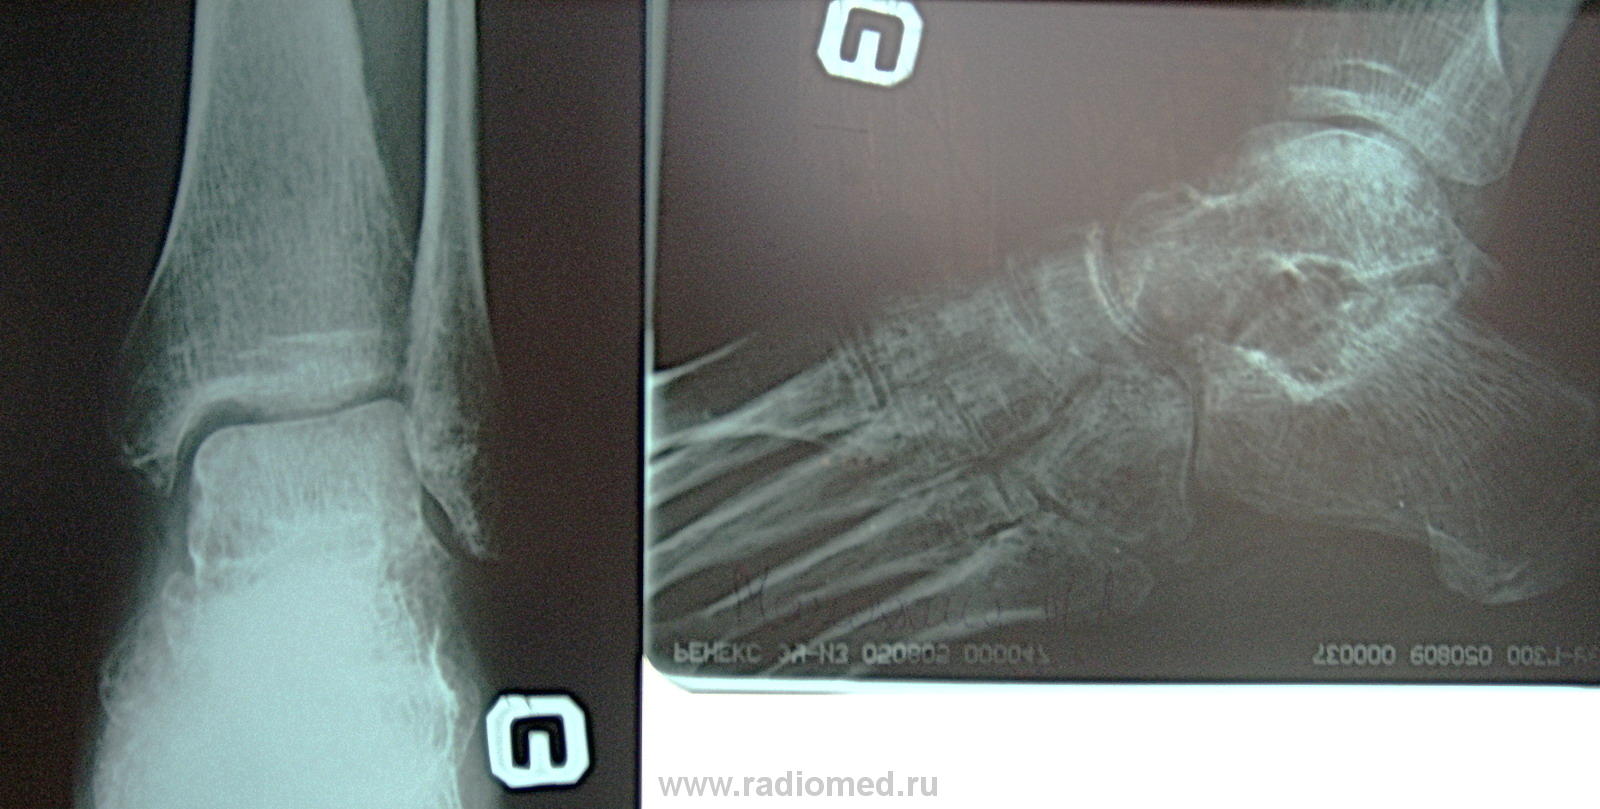

Женщина 40 лет попапла в ДТП. Была сбита машиной и проходила лечение по поводу травмы коленного сустава(повреждение мениска). В настоящее время, спустя 1 месяц после снятия гипс. повязки, появились сильные боли в голеностопном суставе, особенно, когда нога находится в обуви. Сделали снимок. Насторожила таранная и пяточная кости. Что посоветуют уважаемые коллеги? Моё мнение такое, что здесь помимо остеопороза, идёт процесс какой-то деструкции.

Игорь Артурович, боковой снимок мне видится одной сплошной деструкцией.

Это пятнистый остеопороз, после длительной иммобилизации. Если есть сомнения, сделайте с нагрузкой, как при плоскостопии.

можно снять обе стопы в боковой с нагрузкой так же думаю, что пятнистый остоепороз

А по-моему эти снимки не могут принадлежать сороколетнему человеку?

В данном случае, ключеввым является не столько "нагрузка" (т.е. плоскостопие), сколько стандартизованные условия боковых снимков обеих стоп, и сравнение больной стопы со  здоровой. Т.е. некоторая смена ракурса.

+ за пятнистый остеопороз. Больной не провели нормальную реабилитацию и сразу же дали нагрузку на порозные кости - вот вам и боли. Деструкции никакой нет.